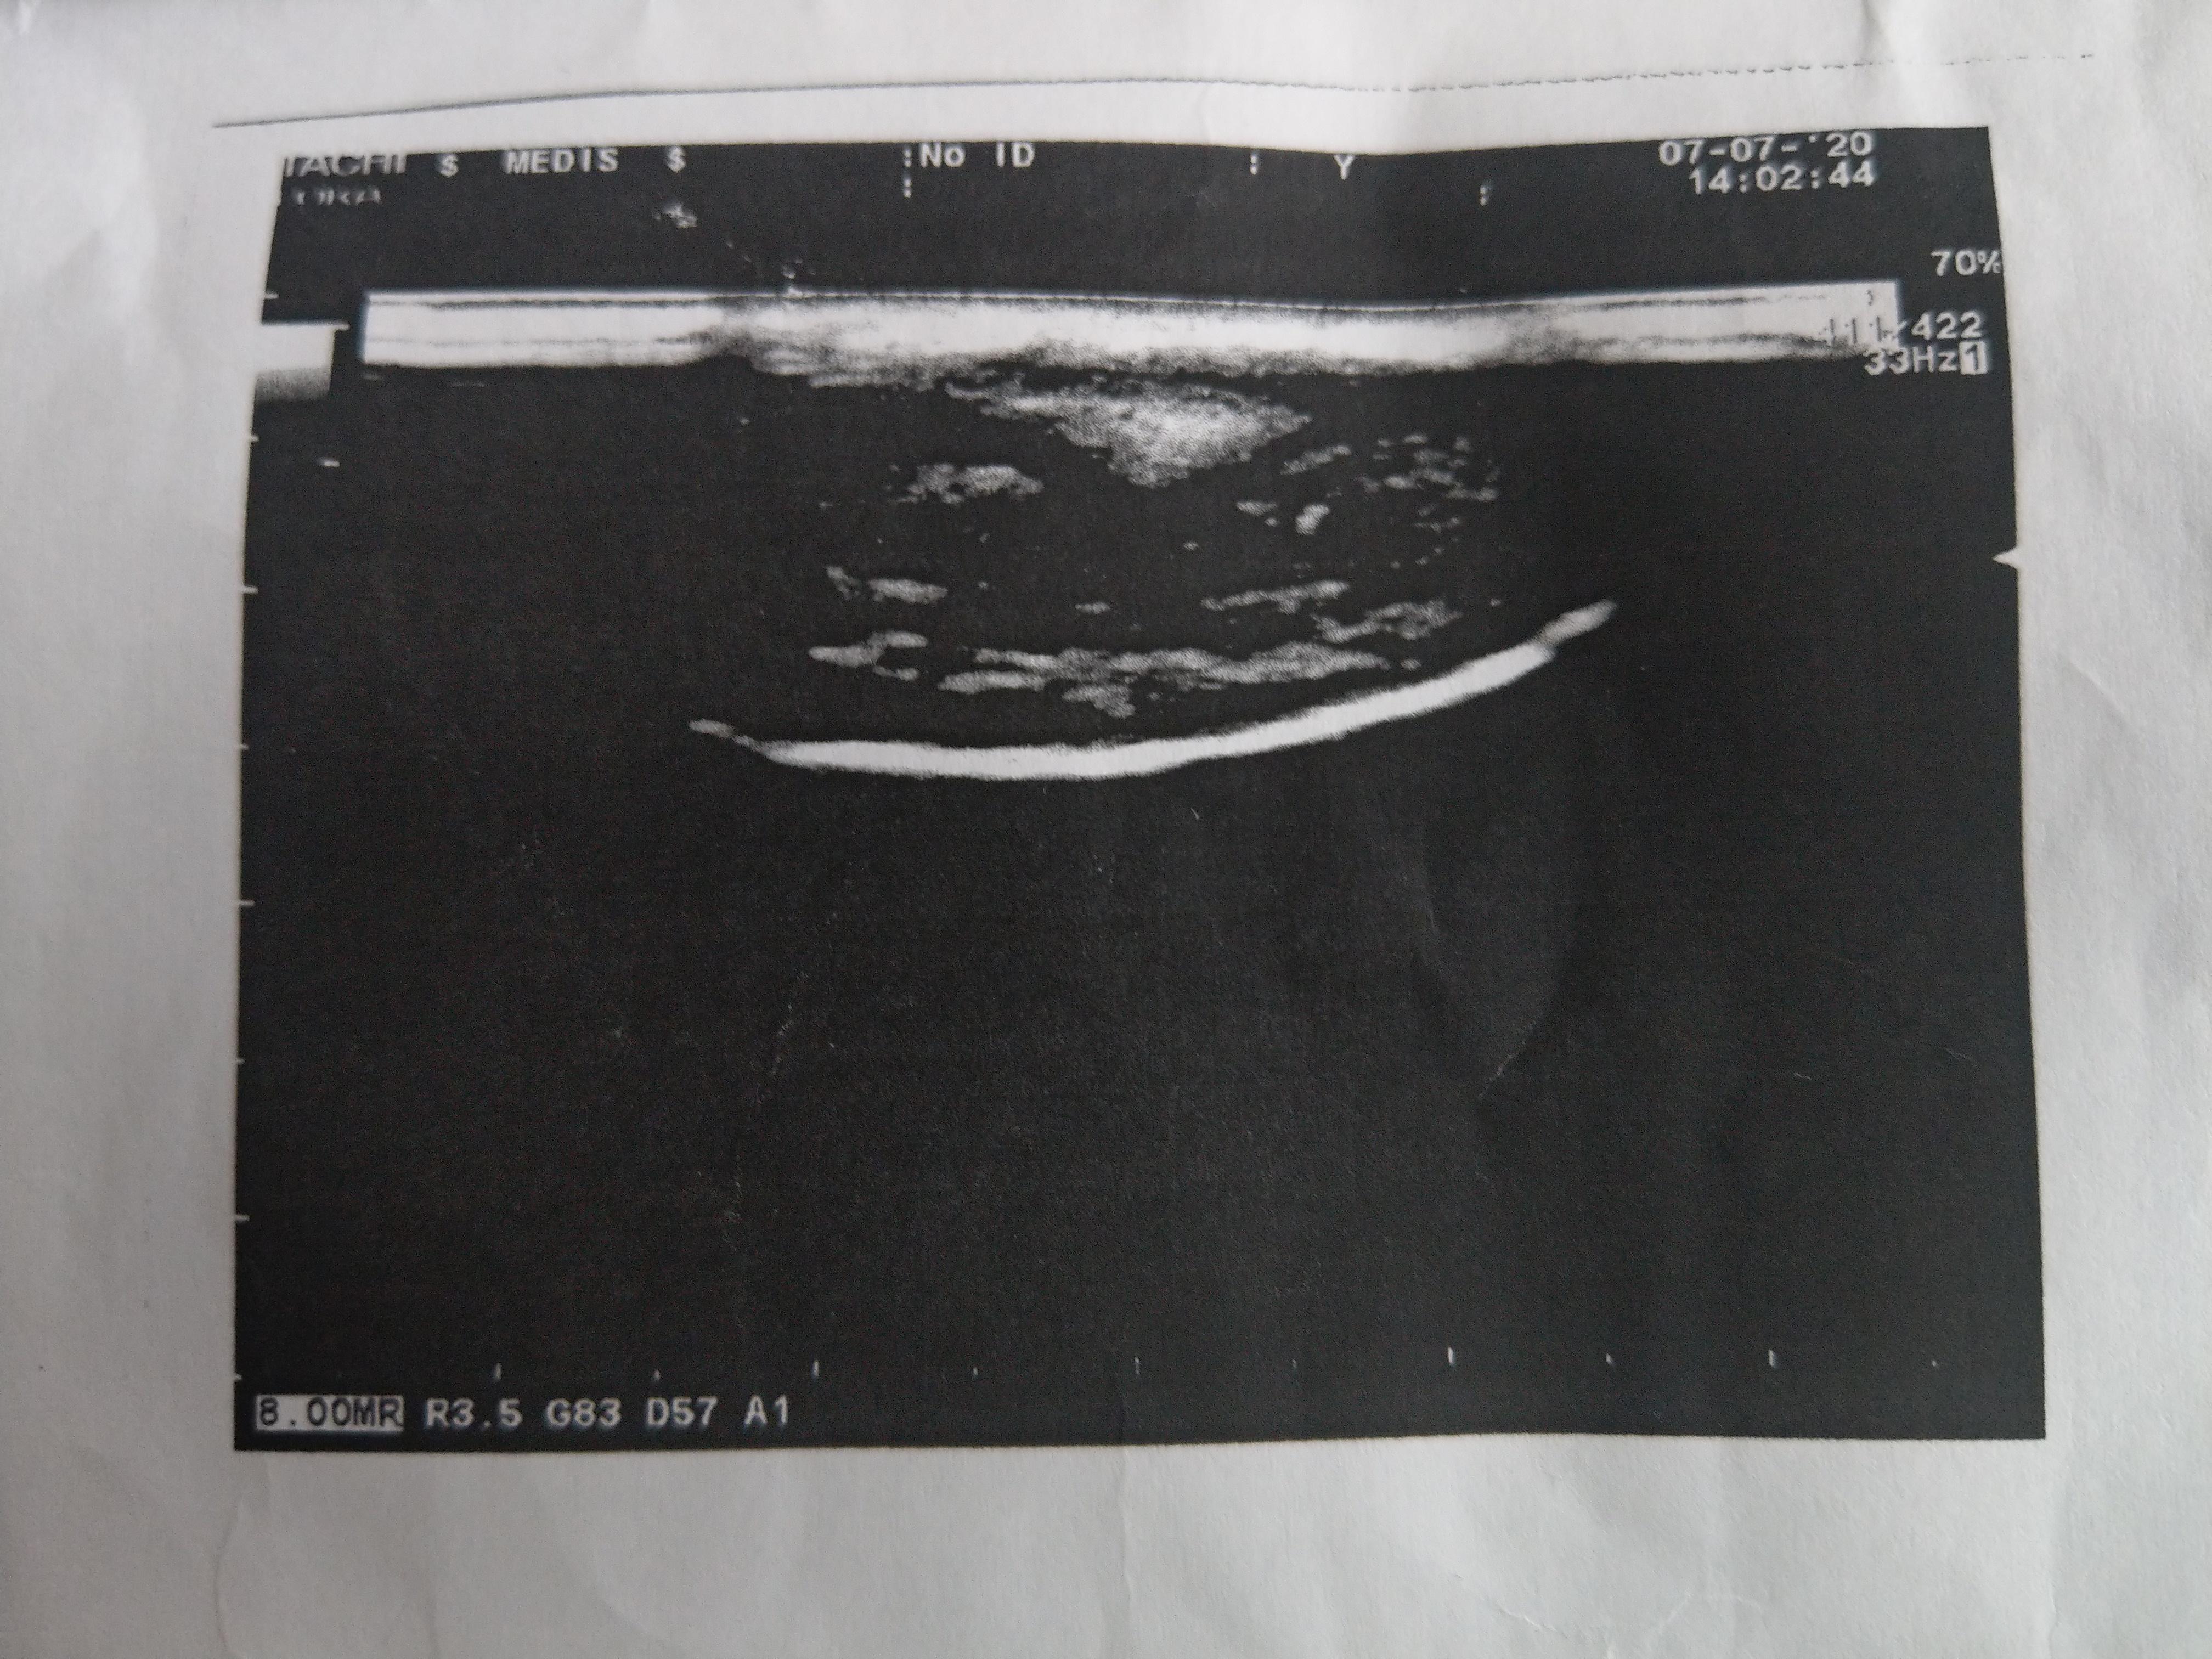

здравствуйте. Около недели назад нащупал ближе к головке полового члена уплотнение. При эрекции легкий дискомфорт, после секса с супругой уплотнение немного увеличилось. Не чешится, не зудит. Был у трех урологов, три разных диагноза, пейрони, кавернит и еще что то. Можете ли по фото с узи сказать что либо ? Других врачей у нас нет к сожалению. Выписали три рецепта..чем и что лечить не пойму))

Здравствуйте! По УЗИ - похоже на формирующуюся бляшку, хотя желательно смотреть ролик с исследованием. Можно рекомендовать комлекс Пейрофлекс - воздействует на различные механизмы образования рубцовой ткани, позволяющие облегчить состояние при болезни Пейрони и замедлить развитие бляшки.